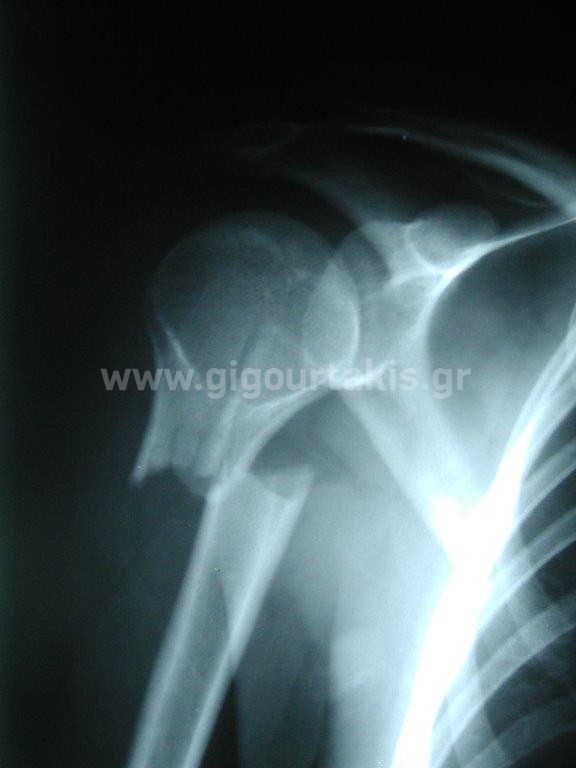

ΚΑΤΑΓΜΑ ΒΡΑΧΙΟΝΙΟΥ ΚΑΤΑΓΜΑ ΔΙΑΦΥΣΗΣ ΒΡΑΧΙΟΝΙΟΥ ΣΥΝΤΗΡΗΤΙΚΑ ΠΕΡΙΣΤΑΤΙΚΟ 1 01. 02. 03.ΑΡΧΙΚΗ ΚΑΜΨΗ ΩΜΟΥ 04.ΑΡΧΙΚΗ ΕΞΩ ΣΤΡΟΦΗ ΩΜΟΥ 05.ΤΕΛΙΚΗ ΚΑΜΨΗ ΩΜΟΥ 06.ΤΕΛΙΚΗ ΑΠΑΓΩΓΗ ΩΜΟΥ 07.ΤΕΛΙΚΗ ΕΞΩ ΣΤΡΟΦΗ ΩΜΟΥ 08.ΤΕΛΙΚΗ ΟΠΙΣΘΙΑ ΠΡΟΣΑΓΩΓΗ ΩΜΟΥ Στις κατηγορίες:ΑΝΩ ΑΚΡΟ, ΣΥΝΤΗΡΗΤΙΚΑ, ΚΑΤΑΓΜΑ ΔΙΑΦΥΣΗΣ ΒΡΑΧΙΟΝΙΟΥ, ΚΑΤΑΓΜΑ ΒΡΑΧΙΟΝΙΟΥ, ΩΜΙΚΗ ΖΩΝΗ ΒΡΑΧΙΟΝΙΟ